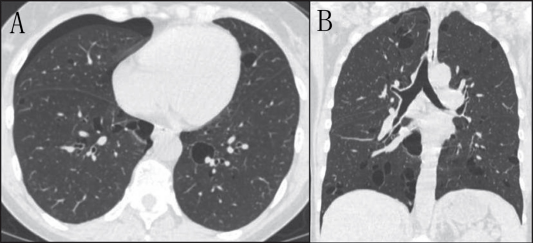

囊肿常见于约2/3的LIP患者,可能是由于血管阻塞引起缺血、阻塞后肺泡扩张或淋巴组织压迫细支气管,形成了活瓣结构。囊肿直径通常可达30mm,薄壁,形态各异,弥漫分布,主要分布于肺下叶和支气管血管束周围(图3)。其他有助于LIP诊断的CT改变包括磨玻璃影和局灶性实变、支气管血管束周围间质增厚和边界不清的小叶中心结节。更少见的是小叶间隔增厚、网状影、胸膜下结节引起的胸膜增厚,以及纵隔或肺门淋巴结肿大(2)。在没有明确诊断系统性疾病的情况下,建议通过组织学确诊LIP。

3 。女性淋巴细胞间质性肺炎干燥综合征患者。胸部CT 扫描显示主要分布为肺叶的磨玻璃影、网状和囊肿。